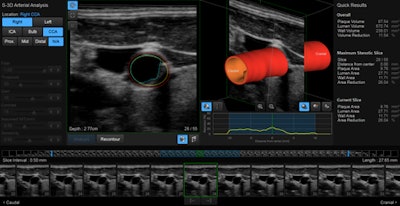

On the Samsung stand, visitors can see a demonstration of the company's latest cardiovascular ultrasound technology. Called S-3D Arterial Analysis, this function supports earlier detection of disease by executing both morphological and functional analysis of the vasculature. It enables a quantitative 3D analysis that estimates the volume of plaque within the vessel and calculates the distance to adjoining anatomical features, providing a more confident diagnosis and easier examination, the company noted.